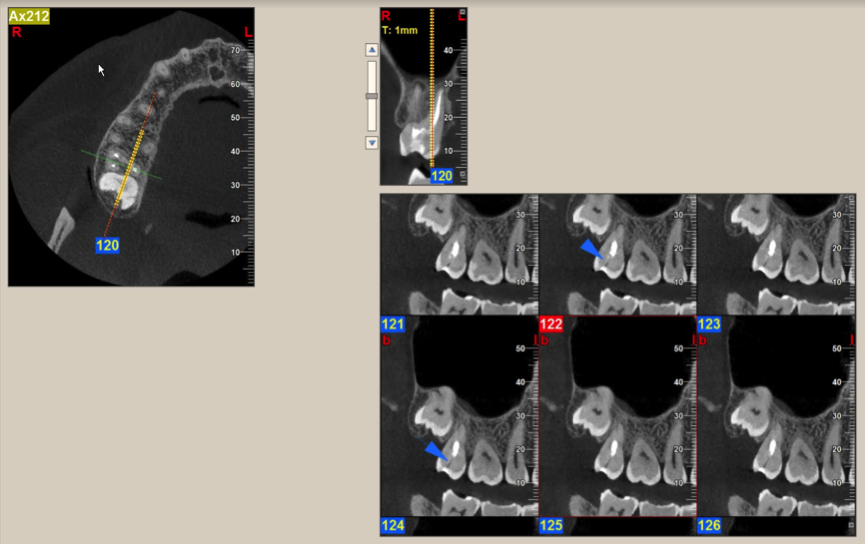

5. Analyze All Available Images with the Proper Diagnostic Utilities

After all of the available diagnostic information is collected, the area of interest is assessed from all perspectives in order to correlate the reported or observed clinical findings to possible changes in the radiologic appearance of the hard tissues in the affected site. This includes a comparison of the region with the contralateral side to evaluate for possible asymmetry or unilateral irregularities of the anatomical structures; altered appearance of known tissues/structures; possible alteration, discontinuity, or even destruction of osseous boundaries; possible shape changes in known anatomical structures; possible mass development and features of the developing mass; possible effects of a mass on known anatomical structures and boundaries; and more (Figure 5). An accurate description of the entity under investigation will reveal useful information about the tissue of origin, its structure (ie, hollowed, cystic, or solid), and its nature (fast growing/aggressive or slow growing/subtle). In the end, a list containing all collected radiologic data should be compiled and used to create a differential diagnostic list consisting of all possible pathological entities that fit the collected descriptive data.

During data collection, all available diagnostic utilities should be used, including tools for assessing measurement, angle estimation, bone density, image orientation, and more. All are part of the goal to establish a diagnostic list that is as accurate as possible.